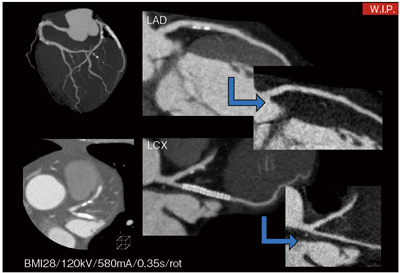

現在,この冠動脈サブトラクションに関しては,岩手医科大学病院附属病院循環器医療センター様と共同研究を行っており,近い将来実用化をめざしている(図4)。

図4 冠動脈サブトラクション画像 (画像ご提供:岩手医科大学附属病院 循環器医療センター様)

図4 冠動脈サブトラクション画像

(画像ご提供:岩手医科大学附属病院 循環器医療センター様)